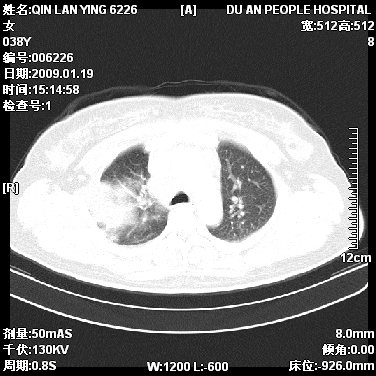

女,38岁,胸疼1个月。wbc:1万4

1)右肺中央型肺癌并右肺上叶阻塞性肺炎、节段性肺不张,纵隔淋巴结转移、右侧胸膜转移、肝脏转移。2)右侧胸腔少量积液。

1、右侧中央型肺癌并阻塞性肺不张,纵隔内、主动脉弓旁、右肺门淋巴结及肝脏转移可能性大,建议纤支镜进一步检查。

2、右侧胸腔积液。

本病例有几个容易诊断的地方:1、右肺上叶前段支气管闭塞,肺不张。2、淋巴结明显肿大。3、肝脏多个类圆形低密度影呈“牛眼征”改变,高度提示转移。

从影像学角度分析      右肺上叶中央型肺癌,并阻塞性不张、肺炎,纵隔淋巴结、膈顶淋巴结转移。

肝内两个大小不等低密度结节,内可见更低密度影,首先考虑肝内转移瘤,但联想到患者wbc1万4,建议楼主还是做个增强比较明确,除外肝脓肿的可能。